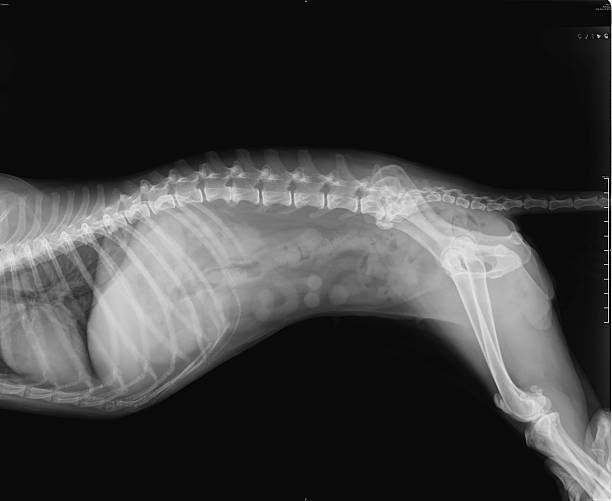

O raio x para cães é um procedimento não invasivo que permite a visualização de ossos, órgãos e tecidos internos dos animais de forma detalhada.

Com ele, é possível identificar fraturas, inflamações, corpos estranhos, tumores, entre outras condições que podem afetar a saúde dos pets. Na Wellpet, o exame de raio x é realizado com todo cuidado e segurança, garantindo resultados precisos para um diagnóstico assertivo.